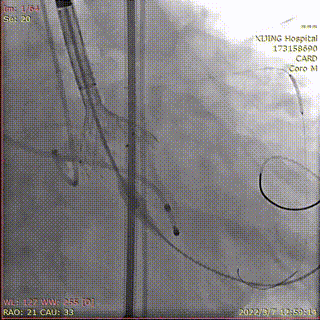

预置4.0*35mm冠脉支架左冠保护并根部造影

冠脉支架置于左主干并造影

造影显示左冠通畅

术后造影显示瓣膜位置理想,冠脉充盈正常